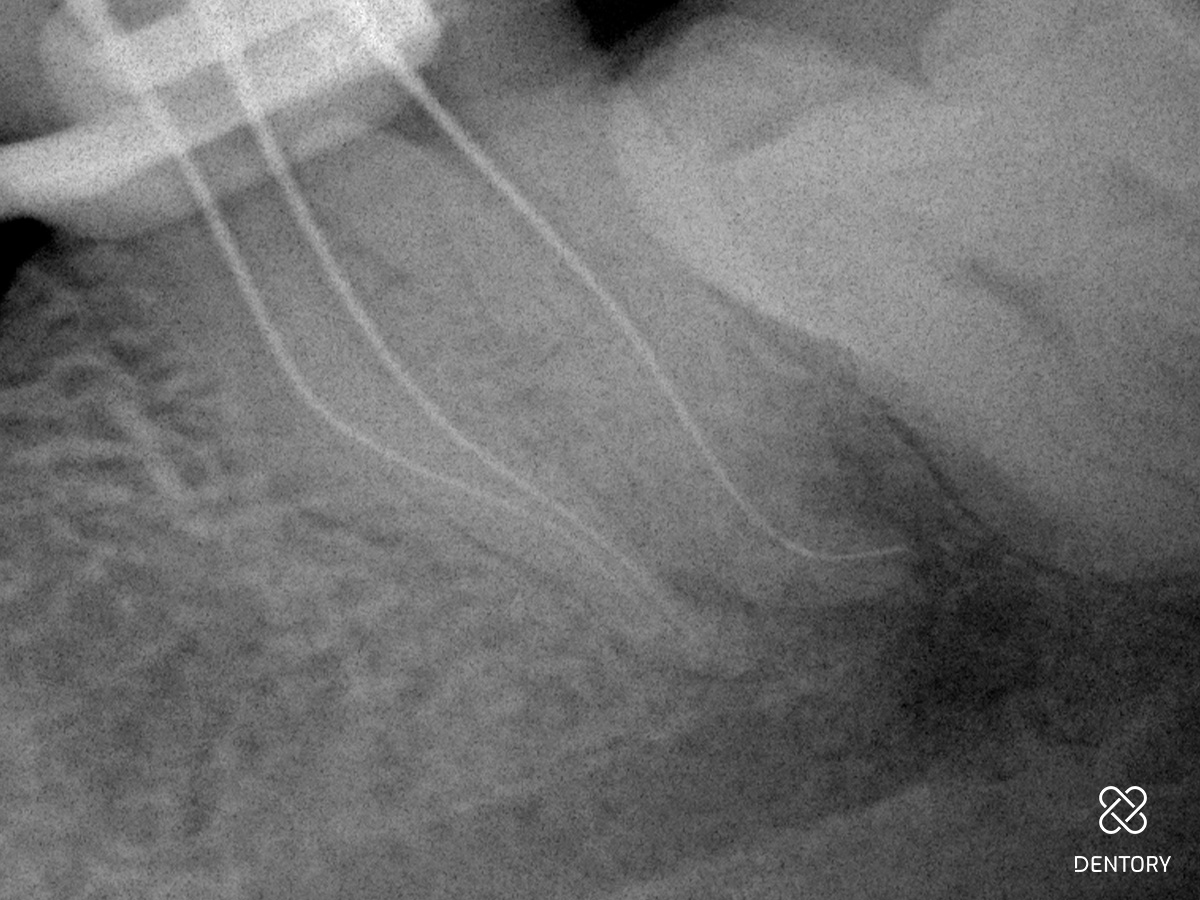

Abbildung 2

Röntgen-Messaufnahme: Aufgrund der Kanalkrümmung erfolgte die Messaufnahme bereits nach der Erstellung eines Gleitpfades bis ISO 10. Der mb und ml Kanal verfügen jeweils über ein separates Foramen.